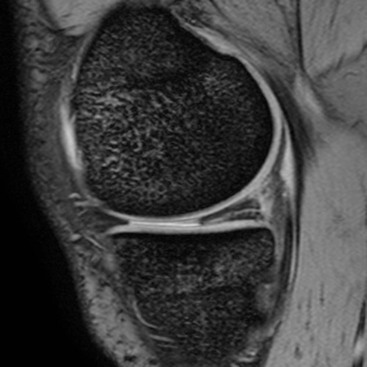

The menisci are two semilunar fibrocartilaginous structures located between the articular cartilage of the femoral and tibial condyles. They each have a crescent shape with an anterior and posterior horn and a body. The tips of the horns are attached to the tibial plateau adjacent to the intercondylar eminence. These attachments are known as the meniscal roots. The medial meniscus is larger than the lateral and has a larger posterior horn than anterior horn. In the case of the lateral meniscus, the horns are of similar size, but in approximately 5% of individuals the lateral meniscus has a discoid morphology. A discoid meniscus is associated with increased incidence of pathology from a young age. Sagittal MRI sequences of the normal meniscus show a bow-tie configuration at the periphery. On progressive images toward the intercondylar fossa the meniscus appears as two triangles representing the anterior and posterior horns. The normal menisci exhibit uniform low signal on all MRI sequences, although in children some increased signal is frequently identified in the posterior third. Degeneration may lead to intrameniscal high signal, or ‘myxoid change’, particularly in the posterior medial meniscus. A tear is diagnosed on MRI when high signal is demonstrated extending to the articular surface of the meniscus. Tears may be horizontal or vertical depending on whether they reach one meniscal surface or two. A complex tear is diagnosed when two or more tear configurations are present. The configuration of a meniscal tear has important implications for management. Horizontal tears are frequently degenerative in nature and may be asymptomatic (Fig. 46-44). Joint fluid may escape through a horizontal tear, forming a parameniscal cyst. Two types of vertical tear are recognised. Longitudinal tears lie within the substance of the meniscus, tracking circumferentially. They often involve the periphery of the meniscus where the blood supply is better and may therefore heal spontaneously. As the name suggests, radial tears extend radially into the meniscus from the free edge; they take several forms. A small oblique slit is a common form and is called a parrot beak tear (Fig. 46-45). If it traverses the full width, a radial tear may split the meniscus, leading to separation of the two parts. A ‘ghost meniscus’ describes the MRI appearance of a complete radial tear where the image section passes through the split (Fig. 46-46). This sign is most often found in tears involving the posterior root of the medial meniscus. Some tears have a fragment which may displace and cause locking; this is particularly common with longitudinal tears, which, in particular, can give rise to a ‘bucket handle’ tear. Here the meniscal fragment remaining attached at both ends flips into the intercondylar notch (Fig. 46-47). The ‘double PCL sign’ describes a sagittal view showing the posterior cruciate ligament (PCL) and a second parallel low signal structure representing the displaced bucket handle fragment of a torn meniscus (Fig. 46-48).